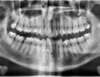

Important encombrement traité par gouttières

A-Début